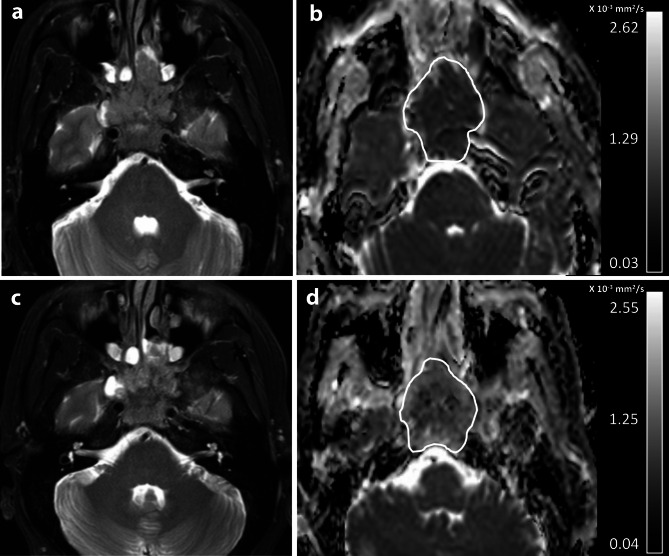

Purpose: To investigate change in diffusion weighted imaging (DWI) between pre-treatment (pre-) and after induction chemotherapy (post-IC) for long-term outcome prediction in advanced nasopharyngeal carcinoma (adNPC).

Materials and methods: Mean apparent diffusion coefficients (ADCs) of two DWIs (ADCpre and ADCpost-IC) and changes in ADC between two scans (ΔADC%) were calculated from 64 eligible patients with adNPC and correlated with disease free survival (DFS), locoregional recurrence free survival (LRRFS), distant metastases free survival (DMFS), and overall survival (OS) using Cox regression analysis. C-indexes of the independent parameters for outcome were compared with that of RECIST response groups. Survival rates between two patient groups were evaluated and compared.

Results: Univariable analysis showed that high ΔADC% predicted good DFS, LRRFS, and DMFS p < 0.05), but did not predict OS (p = 0.40). Neither ADCpre nor ADCpost-IC (p = 0.07 to 0.97) predicted outcome. Multivariate analysis showed that ΔADC% independently predicted DFS, LRRFS, and DMFS (p < 0.01 to 0.03). Compared with the RECIST groups, the ΔADC% groups (threshold of 34.2%) showed a higher c-index for 3-year (0.47 vs. 0.71, p < 0.01) and 5-year DFS (0.51 vs. 0.72, p < 0.01). Compared with patients with ΔADC%<34.2%, patients with ΔADC%≥34.2% had higher 3-year DFS, LRRFS and DMFS of 100%, 100% and 100%, respectively (p < 0.05).

Conclusion: Results suggest that ΔADC% was an independent predictor for long-term outcome and was superior to RECIST guideline for outcome prediction in adNPC. A ΔADC% threshold of ≥ 34.2% may be valuable for selecting patients who respond to treatment for de-escalation of treatment or post-treatment surveillance.